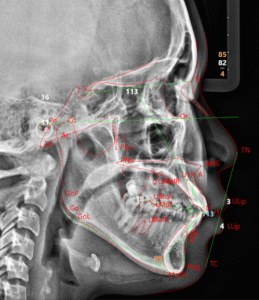

4. セファロ解析

横顔および正面のレントゲン写真(セファロ写真)を専用の分析ソフトで解析し、骨格や歯の角度を数値化します。

・上下顎の位置関係や顔のバランスを精密に評価

・治療後の横顔シミュレーションが可能

・客観的データに基づく診断で安心度が高い